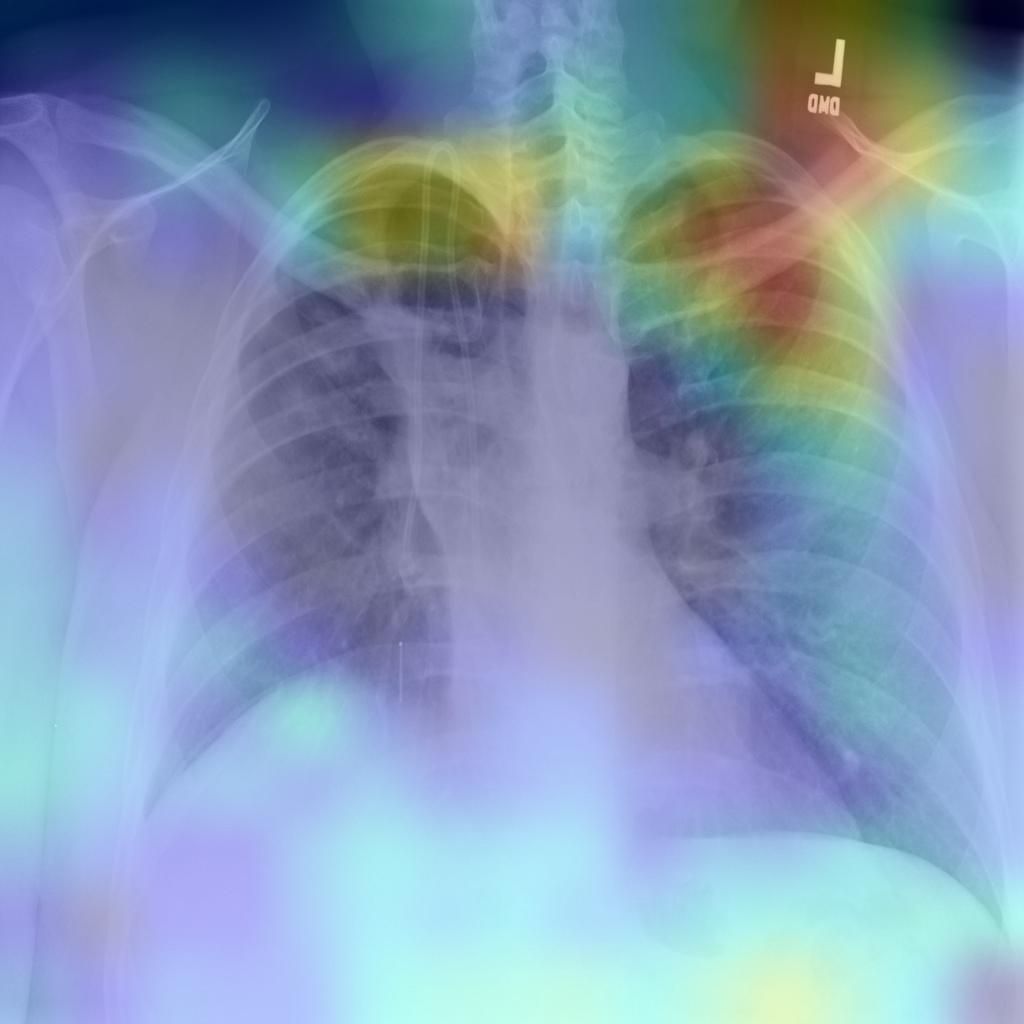

In our evaluation, we applied the Grad-CAM visual interpretation method to visually depict the salient areas where ECOVNet emphasizes the classification decision for a given chest X-ray image. Accurate and definitive salient region detection is crucial for the analysis of classification decisions as well as for assuring the trustworthiness of the results. In order to locate the salient area, the feature weights with various illuminations related to feature importance are used to create a two-dimensional heat map and superimpose it on a given input image. Figure 9 shows the visualization results of locating Grad-CAM using ECOVNet for each model snapshots. This salient area locates the area of each category area in the lung that has been identified when a given image is classified as COVID-19 or normal or pneumonia. As shown in Figure 9, for COVID-19, a ground-glass opacity(GGO) occurs along with some consolidation, thereby partially covering the markings of the lungs. Hence, it leads to lung inflammation in both the upper and lower zones of the lung. When examining the heat maps generated from the COVID-19 chest X-ray, it can be distinguished that the heat maps created from snapshot 2 and snapshot 3 points to the salient area (such as GGO). However, in the case of the normal chest X-ray, no lung inflammation is observed, so there is no significant area, thereby easily distinguishable from other classes, i.e., COVID-19 and pneumonia. As well, it can be observed from the chest X-ray for pneumonia is that there are GGOs in the middle and lower parts of the lungs. The heat maps generated for the pneumonia chest X-ray are localized in the salient regions with GGO, but for the 4th snapshot model, it appears to fail to identify the salient regions as the heat map highlights outside the lung. Accordingly, we believe that the proposed ECOVNet provides sufficient information about the inherent causes of the COVID-19 disease through an intuitive heat map, and this type of heat map can help AI-based systems interpret the classification results achieved from the proposed architecture.

Refer to captionRefer to captionRefer to captionRefer to captionRefer to captionRefer to captionRefer to captionRefer to captionRefer to captionRefer to captionRefer to captionRefer to captionRefer to captionRefer to captionRefer to captionRefer to captionRefer to captionRefer to captioni=1𝑖1i=1i=2𝑖2i=2i=3𝑖3i=3i=4𝑖4i=4i=5𝑖5i=5COVID-19Normal Pneumonia Grad-CAM Visualization for ith Snapshot Model

Figure 9: Grad-CAM visualization for the proposed ECOVNet considering the base model EfficientNet-B5. A total of 5 (five) model snapshots were generated during the training process.